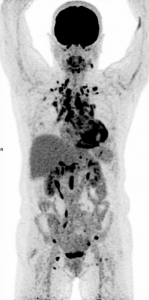

TEP-TDM au 18FDG après régime HFLC (high fat low carbo hydrate):

Hypermétabolisme septal et de la paroi antéro-latérale en rapport avec l’atteinte granulomateuse.

Théoriquement pas de métabolisme des lésions fibreuses.

Lésion granulomateuse septale, inférieure et antéro-latérale concordante avec les lésions hypofixantes scintigraphie au 99mTc-MIBI